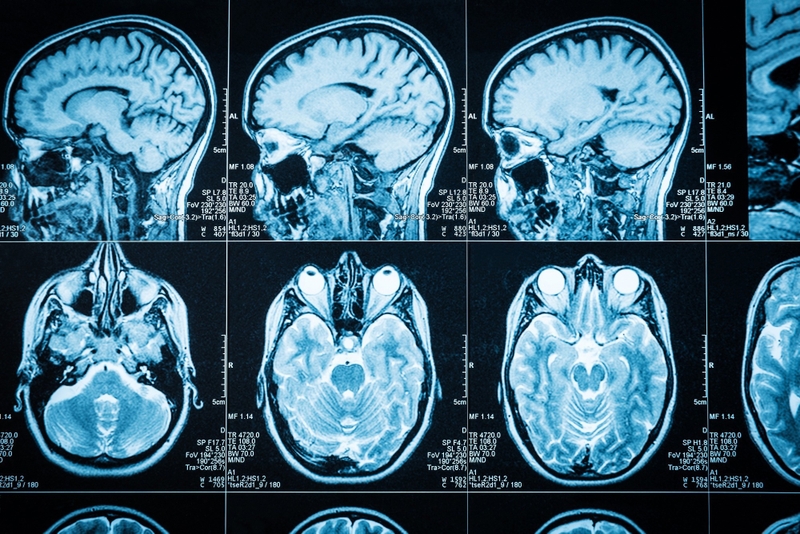

Nang màng nhện là một khối u làm choáng chỗ, lành tính chứa dịch não tủy bên trong nang và vị trí của nang là ở hệ thần kinh trung ương. Đa số các trường hợp nang màng nhện là tổn thương lành tính, có thể nằm ở các vị trí khác nhau như: Nội sọ (đa số nằm ở vị trí trên lều, có hoặc không thông thương với khoang dưới nhện), tủy sống, quanh dây thần kinh. Các vị trí thường gặp nhất của nang màng nhện:

Nang màng nhện nhỏ và không gây triệu chứng trên lâm sàng thường sẽ được theo dõi, thăm khám định kỳ hoặc điều trị bảo tồn. Nhưng khi nang lớn dần hoặc gây chèn ép, tổn thương các cơ quan lân cận như não, tủy sống và gây ra các triệu chứng trên lâm sàng thì sẽ có chỉ định phẫu thuật để cắt bỏ nang. Nội soi phá nang màng nhện là một phương pháp ít xâm lấn và đem lại hiệu quả cao nên thường được lựa chọn.